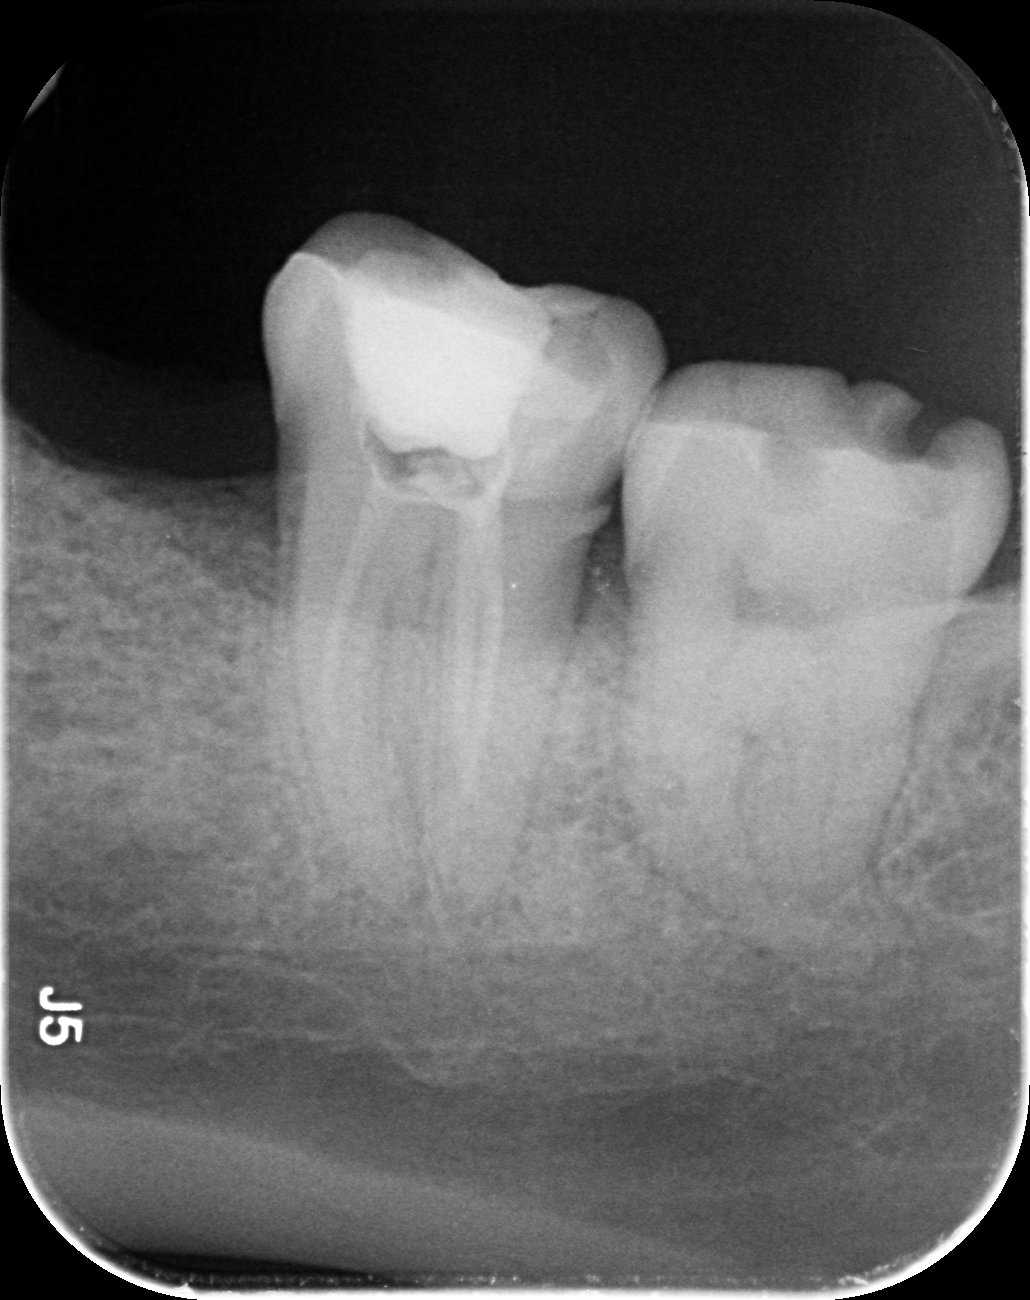

Dantų kanalų gydymas